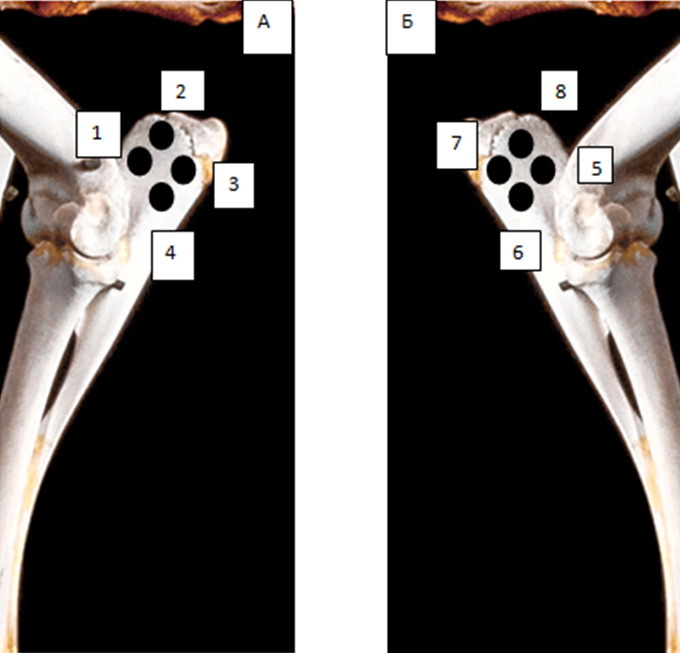

Рис. 3. Схема имплантации биоматериала в локтевой отросток в левой (А) и в правой (Б) локтевых костях овцы

В работе использовалась модель местного действия материала после имплантации в область дефекта костной ткани животных. Дефект представлял собой трепанацию в области локтевых отростков передних правой и левой конечностях (по 4 дефекта в каждом отростке, всего 8 дефектов). Все созданные дефекты имели глубину 5 мм, диаметр 7 мм (рис. 3 и 5А).